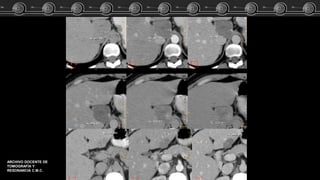

Hemangiomas

Cavernosos

• T1:

hipointensos o isointensos con

respecto a la sangre.

RM

• T2:

Hiperintensos.

• T1 + C:

Igual patrón de captación que

en la TC.